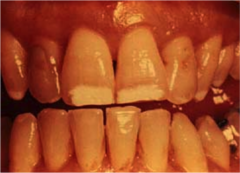

erosion

-loss of tooth structure w/ smooth polished surface -cause: chemical action, bulemia